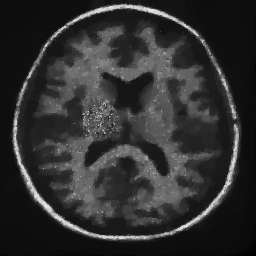

4.1. Uniform Gaussian noise

In this first experiment, we consider the denoising problem with brain scan images. The first set consists of images of pixels and Gaussian noise with zero mean and variance . The original and noisy images are shown in Figure 4.1. The domain decomposition-semismooth Newton algorithms run with the parameter values , , and . The results are shown in Figure 4.2. From the surface representation of , we can observe that is continuous and its shape is related to the one of the original image. In particular, the regularization is stronger in homogeneous regions in the image, and weaker where the image intensity undergoes variations on a smaller scale.

In Table 4.1 the performance of the different methods is compared. For all of them, only the first 2 domain decomposition iterations were considered. The total number of SSN iterations differ at most by one. The impact of the domain decomposition method becomes clear when comparing the computing times of the methods, corresponding to one, two and four subdomains. The computing time is significantly reduced. The effect of the optimized transmission conditions can be realized when comparing the gap between subdomains, which is much lower in the case of optimized transmission conditions () than in the standard Schwarz method ().